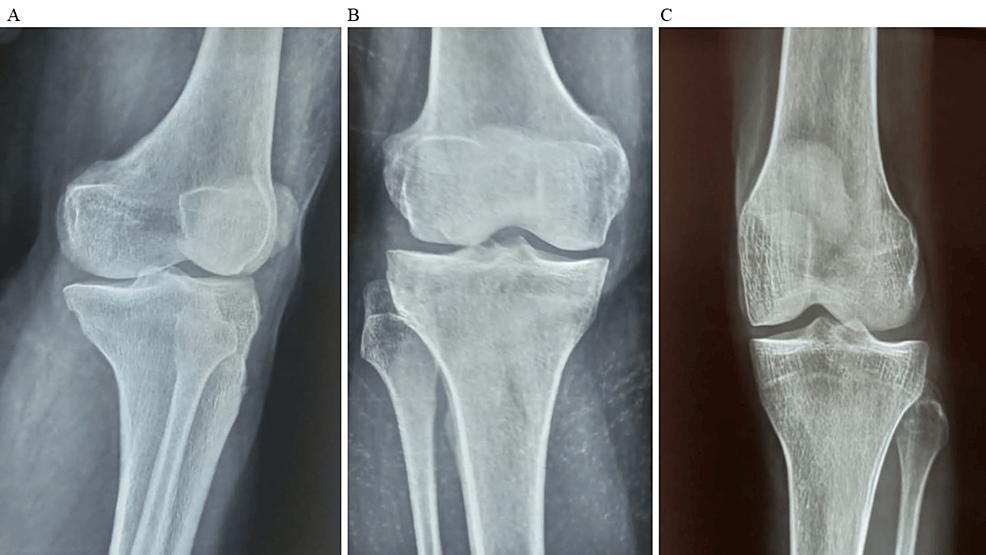

除了骨關(guān)節(jié)炎外,15名參與者還被發(fā)現(xiàn)患有骨缺損,占該隊(duì)列的30%。這些缺損包括各種情況,例如骨折、退行性骨病或先天性畸形,突顯了研究中涉及的骨科問(wèn)題多種多樣。下圖1顯示了開始干細(xì)胞治療之前的骨骼側(cè)視圖和前后視圖。